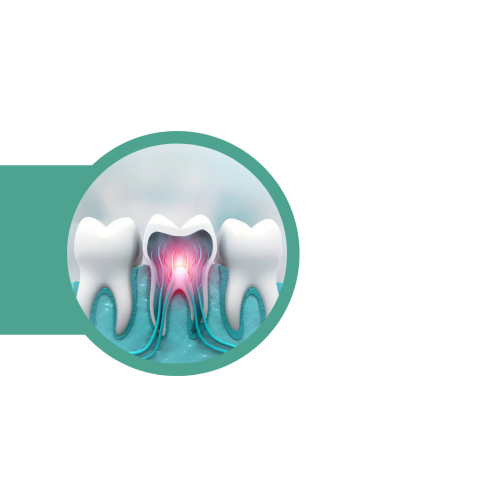

Лечење на

коренски канал

Кога воспалението го зафаќа нервот на забот, се врши третман на коренски канали со цел да се отстрани инфекцијата и да се зачува природниот заб. Постапката е безболна и целосно безбедна.